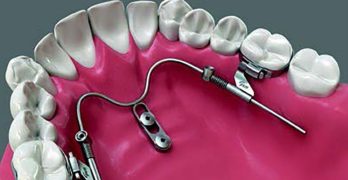

Para comenzar la semana traemos un artículo llamado Asymmetric mandibular arch distalization with third-molar … [Leer más...] acerca de Distalización asimétrica con extracción de terceros molares para la corrección no quirúrgica de la mordida abierta esqueletal clase III y desviación mandibular

Distalización asimétrica con extracción de terceros molares para la corrección no quirúrgica de la mordida abierta esqueletal clase III y desviación mandibular